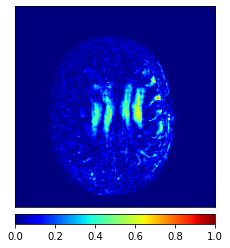

In this paper, we propose a bidirectional learning model, known as dual contrast cycleGAN (DC-cycleGAN), for medical image synthesis from unpaired data. Specifically, a dual contrast (DC) loss is formulated that leverages the advantage of samples from the source domain as negative samples to indirectly build constraints between real source and synthetic images via discriminators, and synthesize images more related to the target domain by enforcing the synthetic images to fall far away from the source domain. In addition, structural similarity index (SSIM) [35] and cross-entropy (CE) [48] are integrated into the DC-cycleGAN structure to avoid disappearing gradient information that is caused by a mean absolute error (MAE) and synthesizing irrelevant images. SSIM considers luminance [35] and CE converges fast as its back-propagation error is less than MSE [28]. As can be seen in Figs. 1 and 2, using SSIM and CE with dual contrast can generate more clear and accurate MR images as compared with that of MAE and MSE, and SSIM and CE without dual contrast loss. Although both SSIM and CE with dual contrast and without dual contrast generate similar CT images, SSIM and CE with dual contrast quantitatively generate better images as shown in Table 4. The experimental results indicate that DC-cycleGAN is able to consider more complex features such as structure in synthesizing images and produce remarkable results as compared with other state-of-the-art methods reported in the literature.

Tables 3 and 4 show the results of MR and CT synthesis, respectively. As can be seen, all components play vital role in both tables. SSIM & CE (w) performs significantly better than other losses in synthesizing MR images. This also can be seen visually in Fig. 1. In contrast, SSIM&CE (w) performs slightly better than SSIM&CE (wo) in synthesizing CT images, both generate more or less similar CT images (see Table 4).